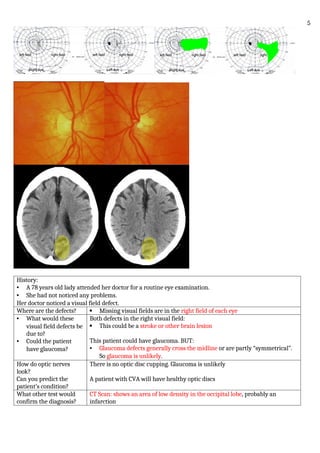

This is a CT image of a

postoperative strabismus

patient.

The alignment of this

patient is most likely:

A. Esotropic

B. Exotropic

C. Cannot tell from this view

D. d. None of the above

The lens of the right eye is oriented outward compared to the straight-ahead orientation

in the left eye.

This image is: A. Axial

B. Coronal

C. Oblique

D. Digital

What is the significant

finding in this image?

How is it treated?

A. Optic nerve changes

B. Fat prolapse

C. Muscle enlargement

D. Right medial rectus slippage

The right medial rectus attaching to sclera well behind the equator. The clinical picture

would also show reduced adduction in this eye. This condition is treated with

advancement of the slipped muscle.